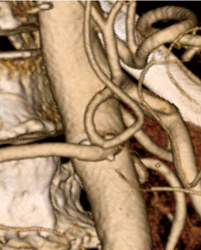

1.CT冠動脈解析

機能改善されたAZE VirtualPlaceの“CT冠動脈解析”は,新たな抽出アルゴリズムを取り入れ,心臓抽出,冠動脈抽出の精度を飛躍的に向上させることに成功した。従来のアルゴリズムでは,造影効果の低いデータの場合血管抽出が不十分であったが,新しく開発したアルゴリズムでは,造影効果が低い場合でも血管が正常に抽出されるように精度向上が行われた。精度のチューニング工程では,各医療機関,モダリティメーカーの協力を受け,各モダリティ画像を利用したチューニングを行った結果,あらゆる医療機関のプロトコールを受け入れやすくなっている。また,この自動抽出精度の飛躍的な向上は,前述のAZE Auto AnalyzerおよびPreset Analyzerの能力を十二分に引き出すことを可能にした。これらの機能使用時のワークフローは劇的に向上する(図3)。

図3 冠動脈自動抽出